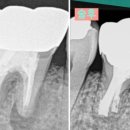

• 박진우치과의원 | [외부 출강] 2023년 9월 서울대병원 전공의 대상 치아 미백 강의 및 실습 진행

관련 물품을 지원받아 강의를 진행하였습니다. 감사합니다. ​ ​ <치과보존과 전문의 박진우> ​ 모든 임상증례의 사진은 환자의 동의하에 진서울치과에서 촬영...보도 목적의 포스트 내용 발췌 시 비밀 댓글로 문의 바랍니다. ​ ​ 진서울치과의원 경기도 성남시 분당구 백현로 105 로얄팰리스 하우스빌 201호 진서울치과의원...

보존과 전문의가 살리는 이야기, 사는 이야기(2023-09-07 12:22:00)